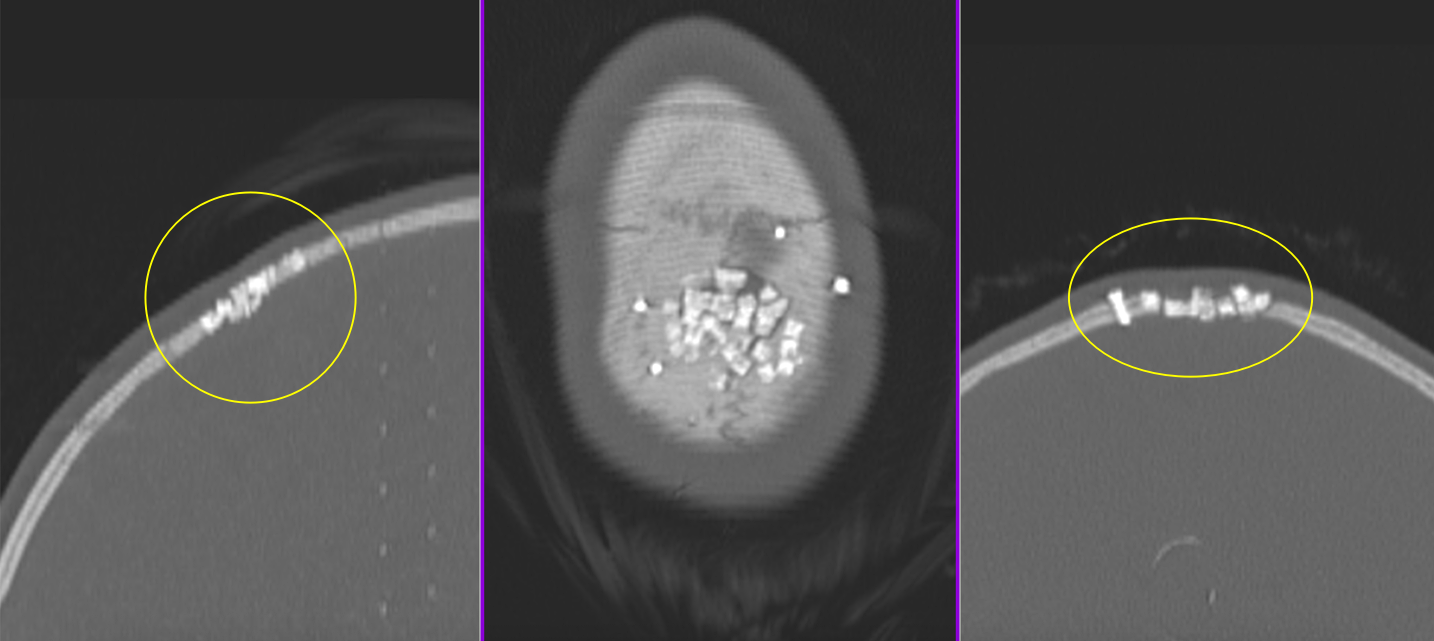

A. Imagistică:

- Radiografie craniană: utilă pentru modificări osoase evidente.

- CT cranian cu reconstrucție 3D: evidențiază detalii osoase.

- RMN cerebral cu contrast: evaluează extensia intracraniană, vasele și nervii implicați.

Este principala formă de tratament pentru tumorile benigne și multe dintre cele maligne. Scop: rezecția completă cu margini negative, menținând funcțiile neurologice. Dacă tumora nu invadează meningele, riscurile neurologice sunt reduse; pe de altă parte, atunci când tumora se extinde și la nivelul durei mater sau chiar al creierului, este posibil ca excizia tumorii să fie subtotală sau parțială, pentru a proteja structurile nervoase.

Un timp important al operației îl reprezintă reconstrucția calotei craniene, care se face cu plăci ceramice customizate, mesh din titan sau ciment acrilic modelat pe loc. Uneori, datorită invaziei tegumentului, sunt necesare intervenții complexe de chirurgie plastică pentru refacerea defectului la nivelul scalpului.